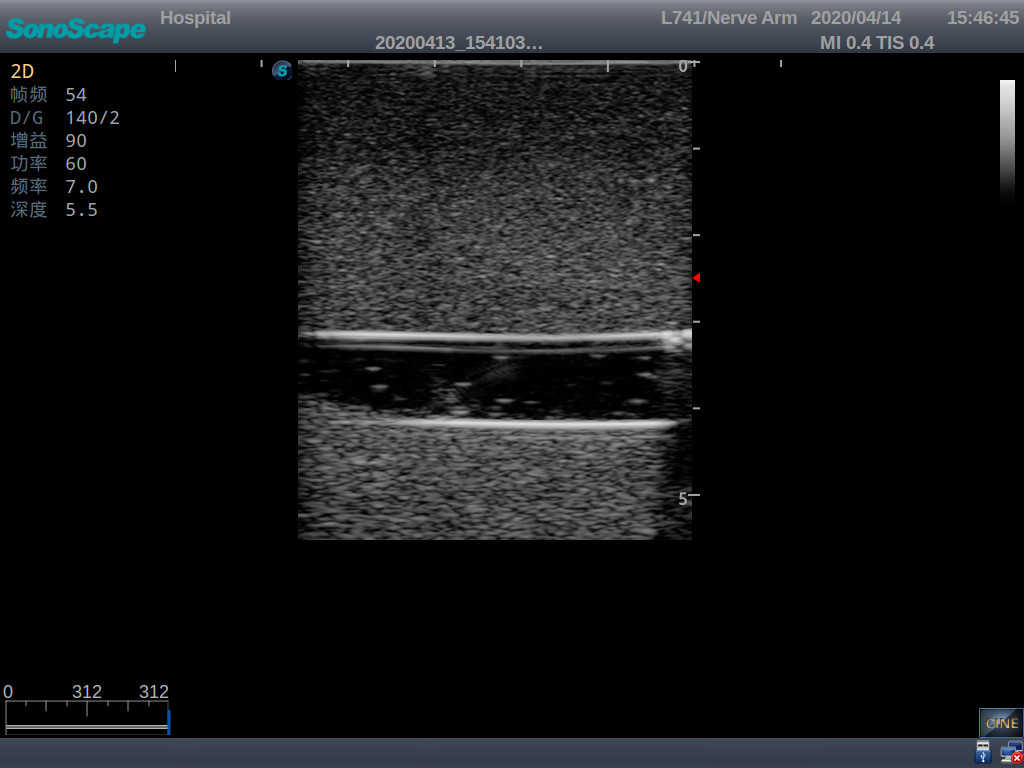

Product size(mm) 700×500×160

It is a model covering up from lobulus auriculae plane to the umbilical plane, and it has anatomical structures like clavicle, rib, sternocleidomastoid, jugular vein and basilic vein.

1)   Made of high molecular polymer ultrasound material, close to the real skin

2)   It can be used by real ultrasound machines

3)   Clear and real images of the tissues and organs (basilic vein and superior vena cava)

5)   Observe the guide wire marches

6)   Detect whether the catheter is properly placed